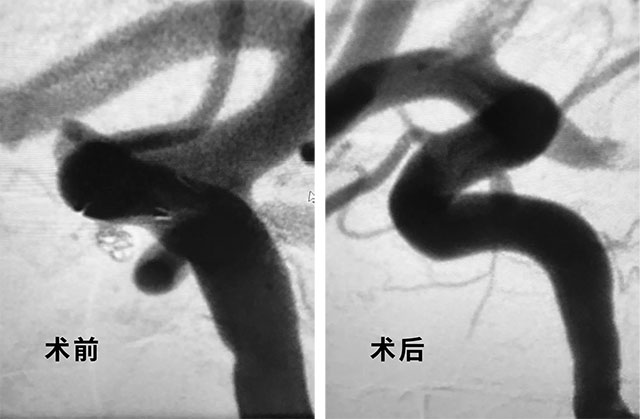

隨后,在蔡女士和家人了解了兩種手術(shù)方法利弊后,他們更傾向于介入治療。在獲得患者和家屬全力支持,手術(shù)準(zhǔn)備就緒后,張琪主任在醫(yī)護(hù)團(tuán)隊(duì)的協(xié)助下于3月19日,為患者進(jìn)行了動(dòng)脈瘤介入栓塞術(shù)。張琪博士順利為患者填入彈簧圈,再置入支架,完全釋放后,造影顯示動(dòng)脈瘤無顯影,支架覆蓋良好,載瘤動(dòng)脈通暢,撤出微導(dǎo)管輸送系統(tǒng),手術(shù)歷經(jīng)2個(gè)小時(shí),順利結(jié)束。

▲ 術(shù)后栓塞成功,造影顯示動(dòng)脈瘤無顯影